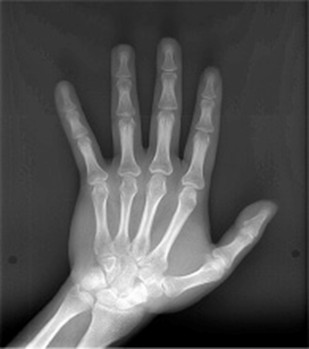

4.歯科矯正と手根骨X線撮影

矯正治療では、患者様の成長段階を正確に把握することが重要です。特にお子様や思春期の患者様では、骨の成長が矯正治療の計画に大きく影響するため、手根骨(手の骨)のX線撮影を行うことがあります。

手根骨の発育は成長期に特定の順序で進むため、この検査を行うことで成長スパート(急激な成長期)のタイミングを予測できます。この情報をもとに、矯正治療の最適な開始時期や治療方法を決定し、より効果的な治療を提供することが可能になります。

特にお子様の矯正では、成長のピークに合わせて治療を行うことで、より良い治療結果が期待できます。

手根骨X線撮影の特徴

- 成長評価に適した検査

手根骨の発達段階を観察することで、個々の成長状況(骨年齢)を把握できます。 - 安全性が高い

低被曝量で、安全に受けられる検査です。 - 矯正治療の適切なタイミングを決定

成長期の矯正治療では、成長スパートの時期を見極めることが重要です。手根骨のX線撮影により、最適なタイミングで矯正を開始し、効率的に治療を進めることができます。 - 成長終了の確認が可能

成人矯正(第Ⅱ期治療)では、骨の成長が完了しているかどうかを判断することが重要です。手根骨撮影を活用することで、顎の成長が完了しているかを正確に評価し、最適な治療計画を立てられます。 - 外科矯正の判断材料になる

顎の成長がどの段階にあるかを確認し、外科手術が必要かどうかを検討する際の判断材料にもなります。 - 個別に最適な治療が可能

年齢だけで判断するのではなく、患者様それぞれの成長状態に応じた矯正計画を立てられるため、無駄のない治療が可能になります。